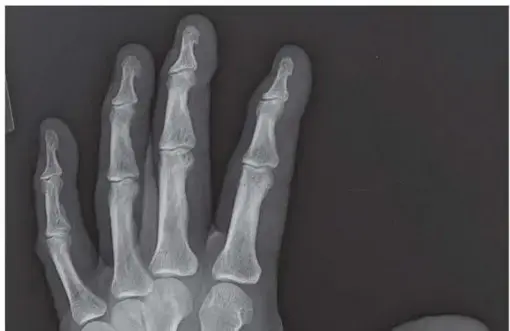

2. الأشعة السينية (X-rays): تُعد الأشعة السينية هي الأداة التشخيصية الأكثر أهمية. يمكنها أن تظهر بوضوح تآكل الغضروف، وتضيق المسافة بين العظام في المفصل، وتكوين نتوءات عظمية (تكوين عظمي جديد) حول المفصل، والتي تعد علامات مميزة لخشونة المفصل.

2. إزالة الغضروف التالف: يتم إزالة أي بقايا غضروفية تالفة من على أسطح عظمتي المفصل (العظم السنعي الأول والعظم المربعي).

4. تثبيت العظام: يتم وضع العظمتين في الوضعية الوظيفية المثلى للإبهام (الوضعية التي تسمح بأفضل استخدام للإبهام في المستقبل)، ثم يتم تثبيتهما معًا باستخدام صفائح ومسامير صغيرة أو أسلاك معدنية. هذه الأدوات تعمل كدعامة مؤقتة حتى تلتئم العظام وتلتحم ببعضها البعض.